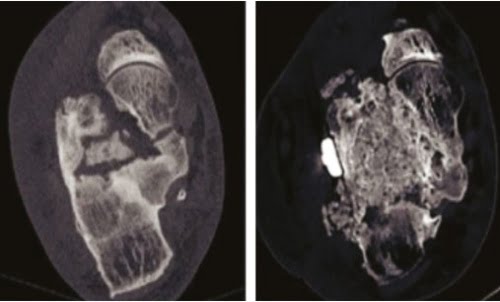

Topuk kemiği kırığı sonrası birden fazla ameliyat sonrasında hem malleol hem de kronik osteomiyelit gelişti.

Orbone® eCOO® Clean kansellöz çipsler ile topuk kemiği kırığı sonrası kronik osteomiyelit tedavisi…